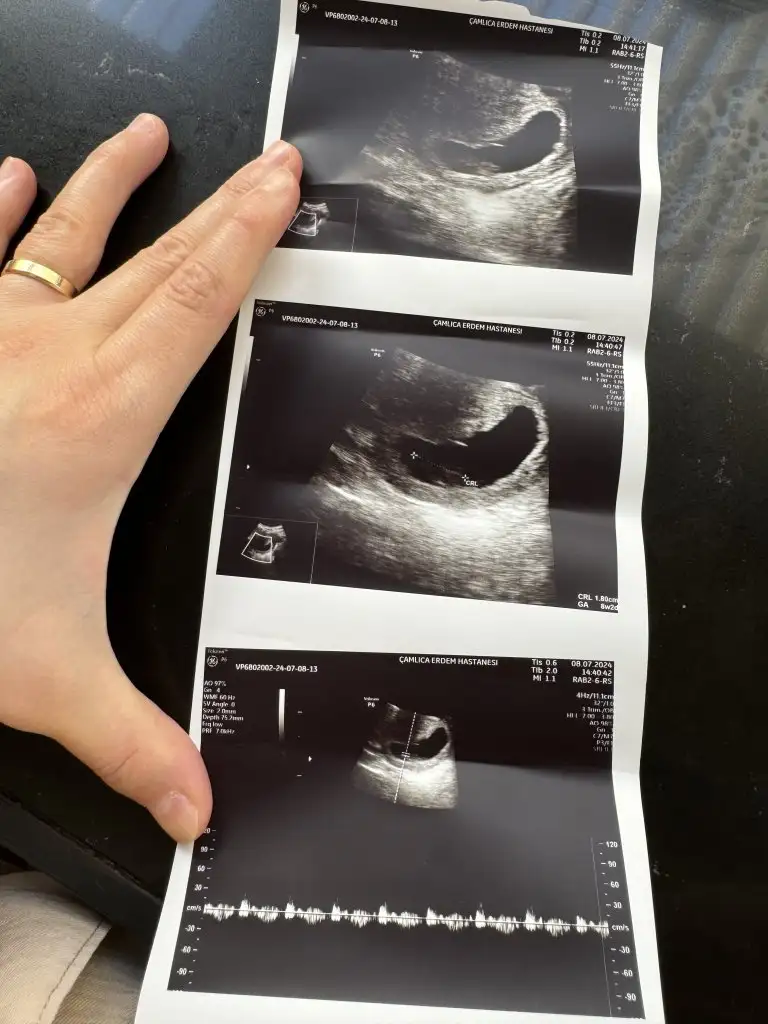

Merhaba bana da bi yorum yapabilir misiniz 8+1 karından